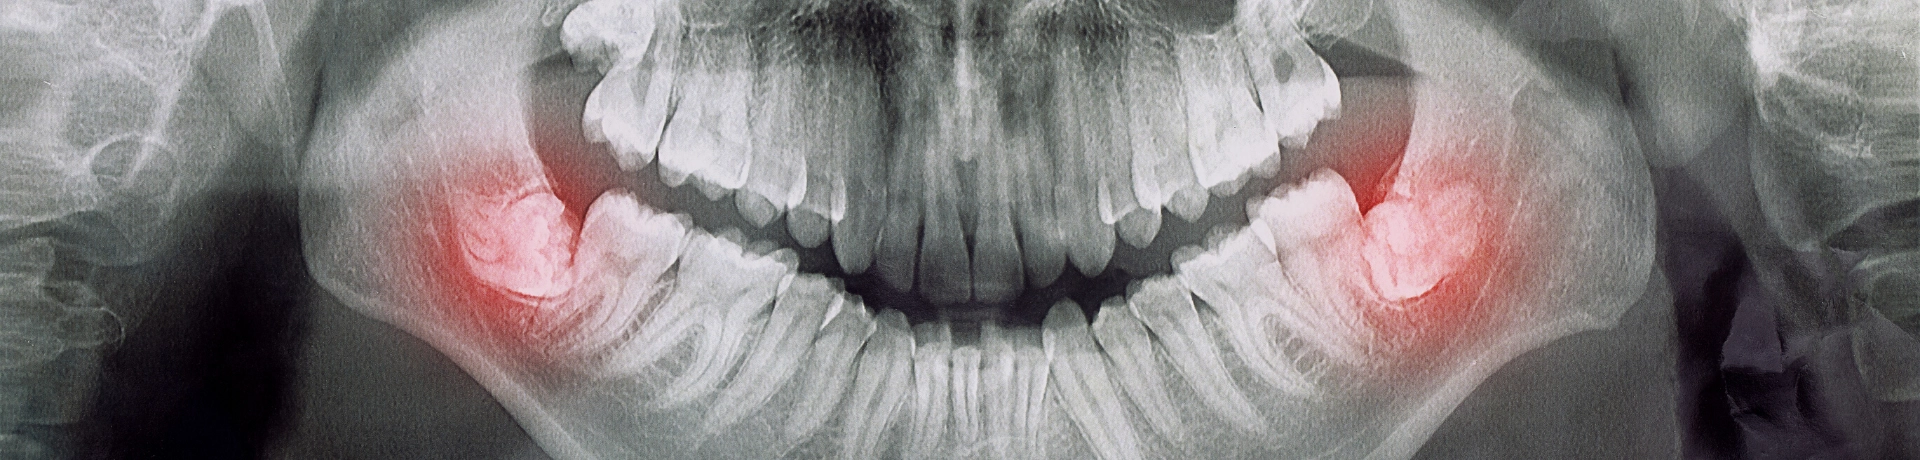

O curso Dentes Inclusos é uma formação destinada a médicos dentistas que desejam especializar-se na área de extração de dentes inclusos, como terceiros molares (sisos) e outros dentes inclusos.

Este curso foca-se na identificação, planeamento e execução de técnicas cirúrgicas seguras para a remoção de dentes inclusos, abordando aspetos anatómicos, avaliação de riscos e métodos de anestesia. Inclui prática clínica supervisionada, onde os participantes podem aprimorar as suas competências em ambientes reais, proporcionando uma base sólida para intervenções complexas na prática clínica diária.